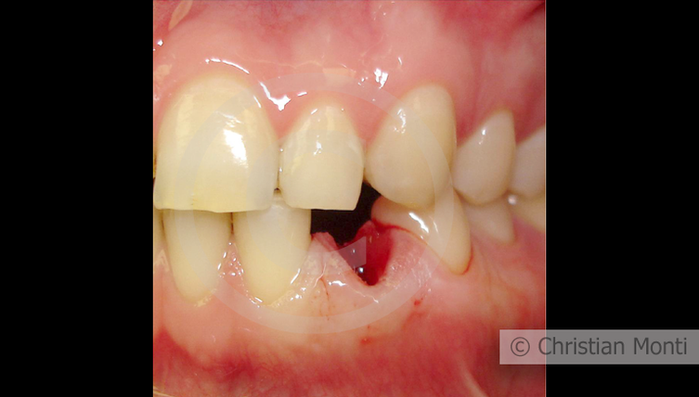

EDENTULIA SINGOLA

Impianto in sostituzione di un canino deciduo